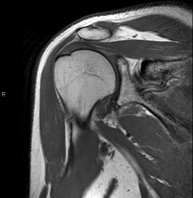

- RM Hombro

Exploración para el estudio de lesiones en tendones, músculos y articulación. Su principal utilidad reside en diagnosticar las lesiones de los tendones del manguito rotador. Tiene una duración aproximada de 20 minutos. No emplea radiación ionizante.